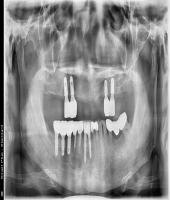

| ● 진료과목 : [임플란트] 치주환자의 임플란트 보철치료

| ● 내용 : 50대 치주환자의 임플란트치료. |